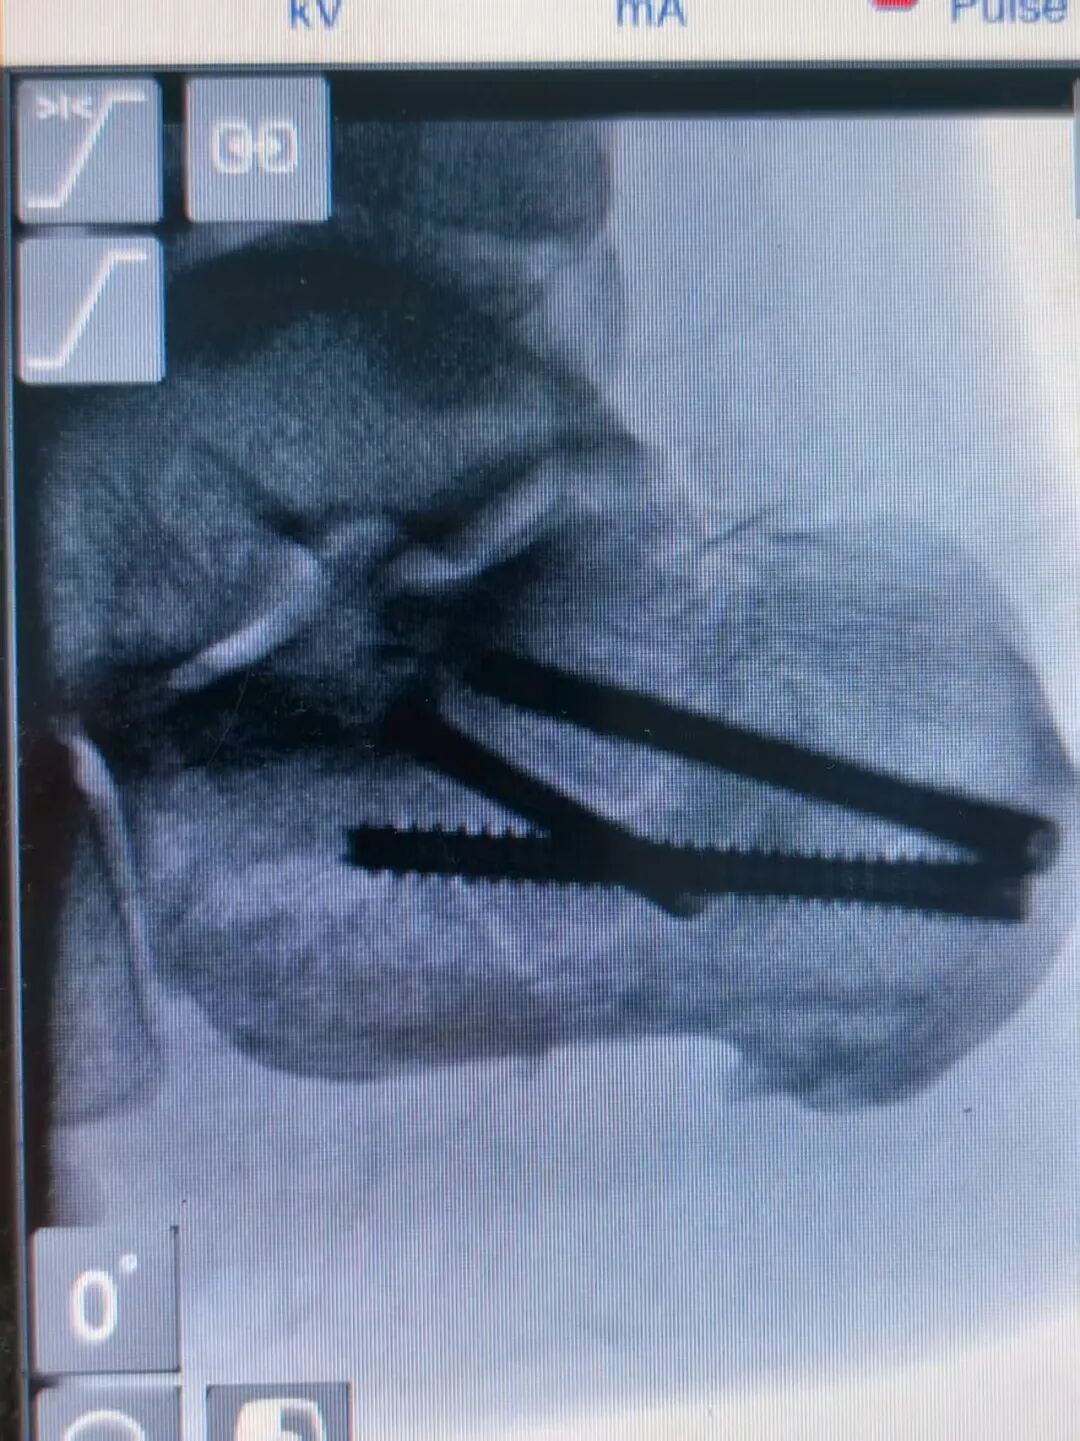

术后